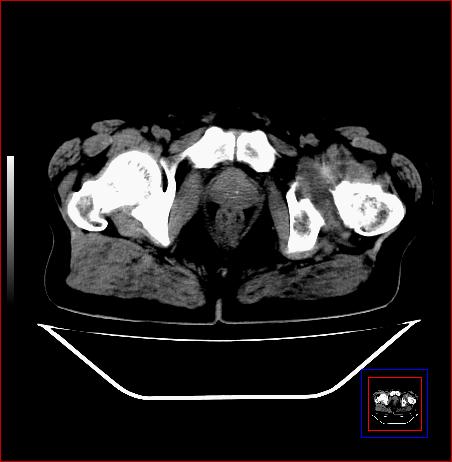

标题: CT15143:髋关节结核?

男,49,髋关节疼痛1年,无肺结核。

支持左侧髋关节结核合并轻度半脱位

骨质破坏,硬化,周围软组织脓肿,支持骨结核

骨质破坏,硬化,周围软组织脓肿,关节间隙增宽,支持骨结核

骨质破坏,硬化,周围软组织脓肿,关节间隙增宽,支持骨结核 .应与无菌坏死鉴别

支持:左侧髋关节结核合并轻度半脱位!

可以是结核,也可以是无菌坏死,还可以是先天髋关节脱位,不结合临床病史,只凭图像鉴别,请各位老师指教。

支持 左侧髋关节结核并半脱位。